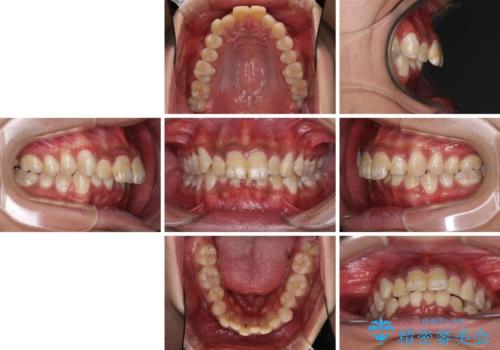

- 深い咬み合わせと前歯のデコボコを改善したいとのことで来院された患者様です。

口元の突出感はないものの、上顎前歯のデコボコが著しく、右側の咬み合わせがずれていたため、上顎右側第一小臼歯1本を抜歯することとしました。

咬合力が非常に強く、抜歯したスペースがなかなか閉じないであろうことは予想できましたが、思っていた以上に期間がかかりました。

前歯のすり減りも著しかったため、仕上げの位置の調整にも期間を要しました。